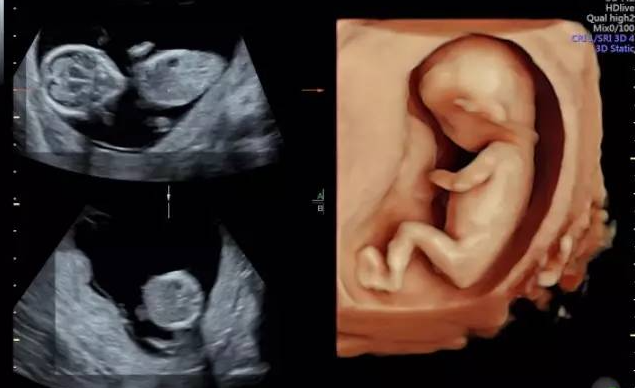

超声影像(四维彩超),不知道这些就白做了

超声影像(四维彩超)是孕期必做项目 不但能早期发现胎儿体表缺陷 还能给宝宝留下珍···【详情】